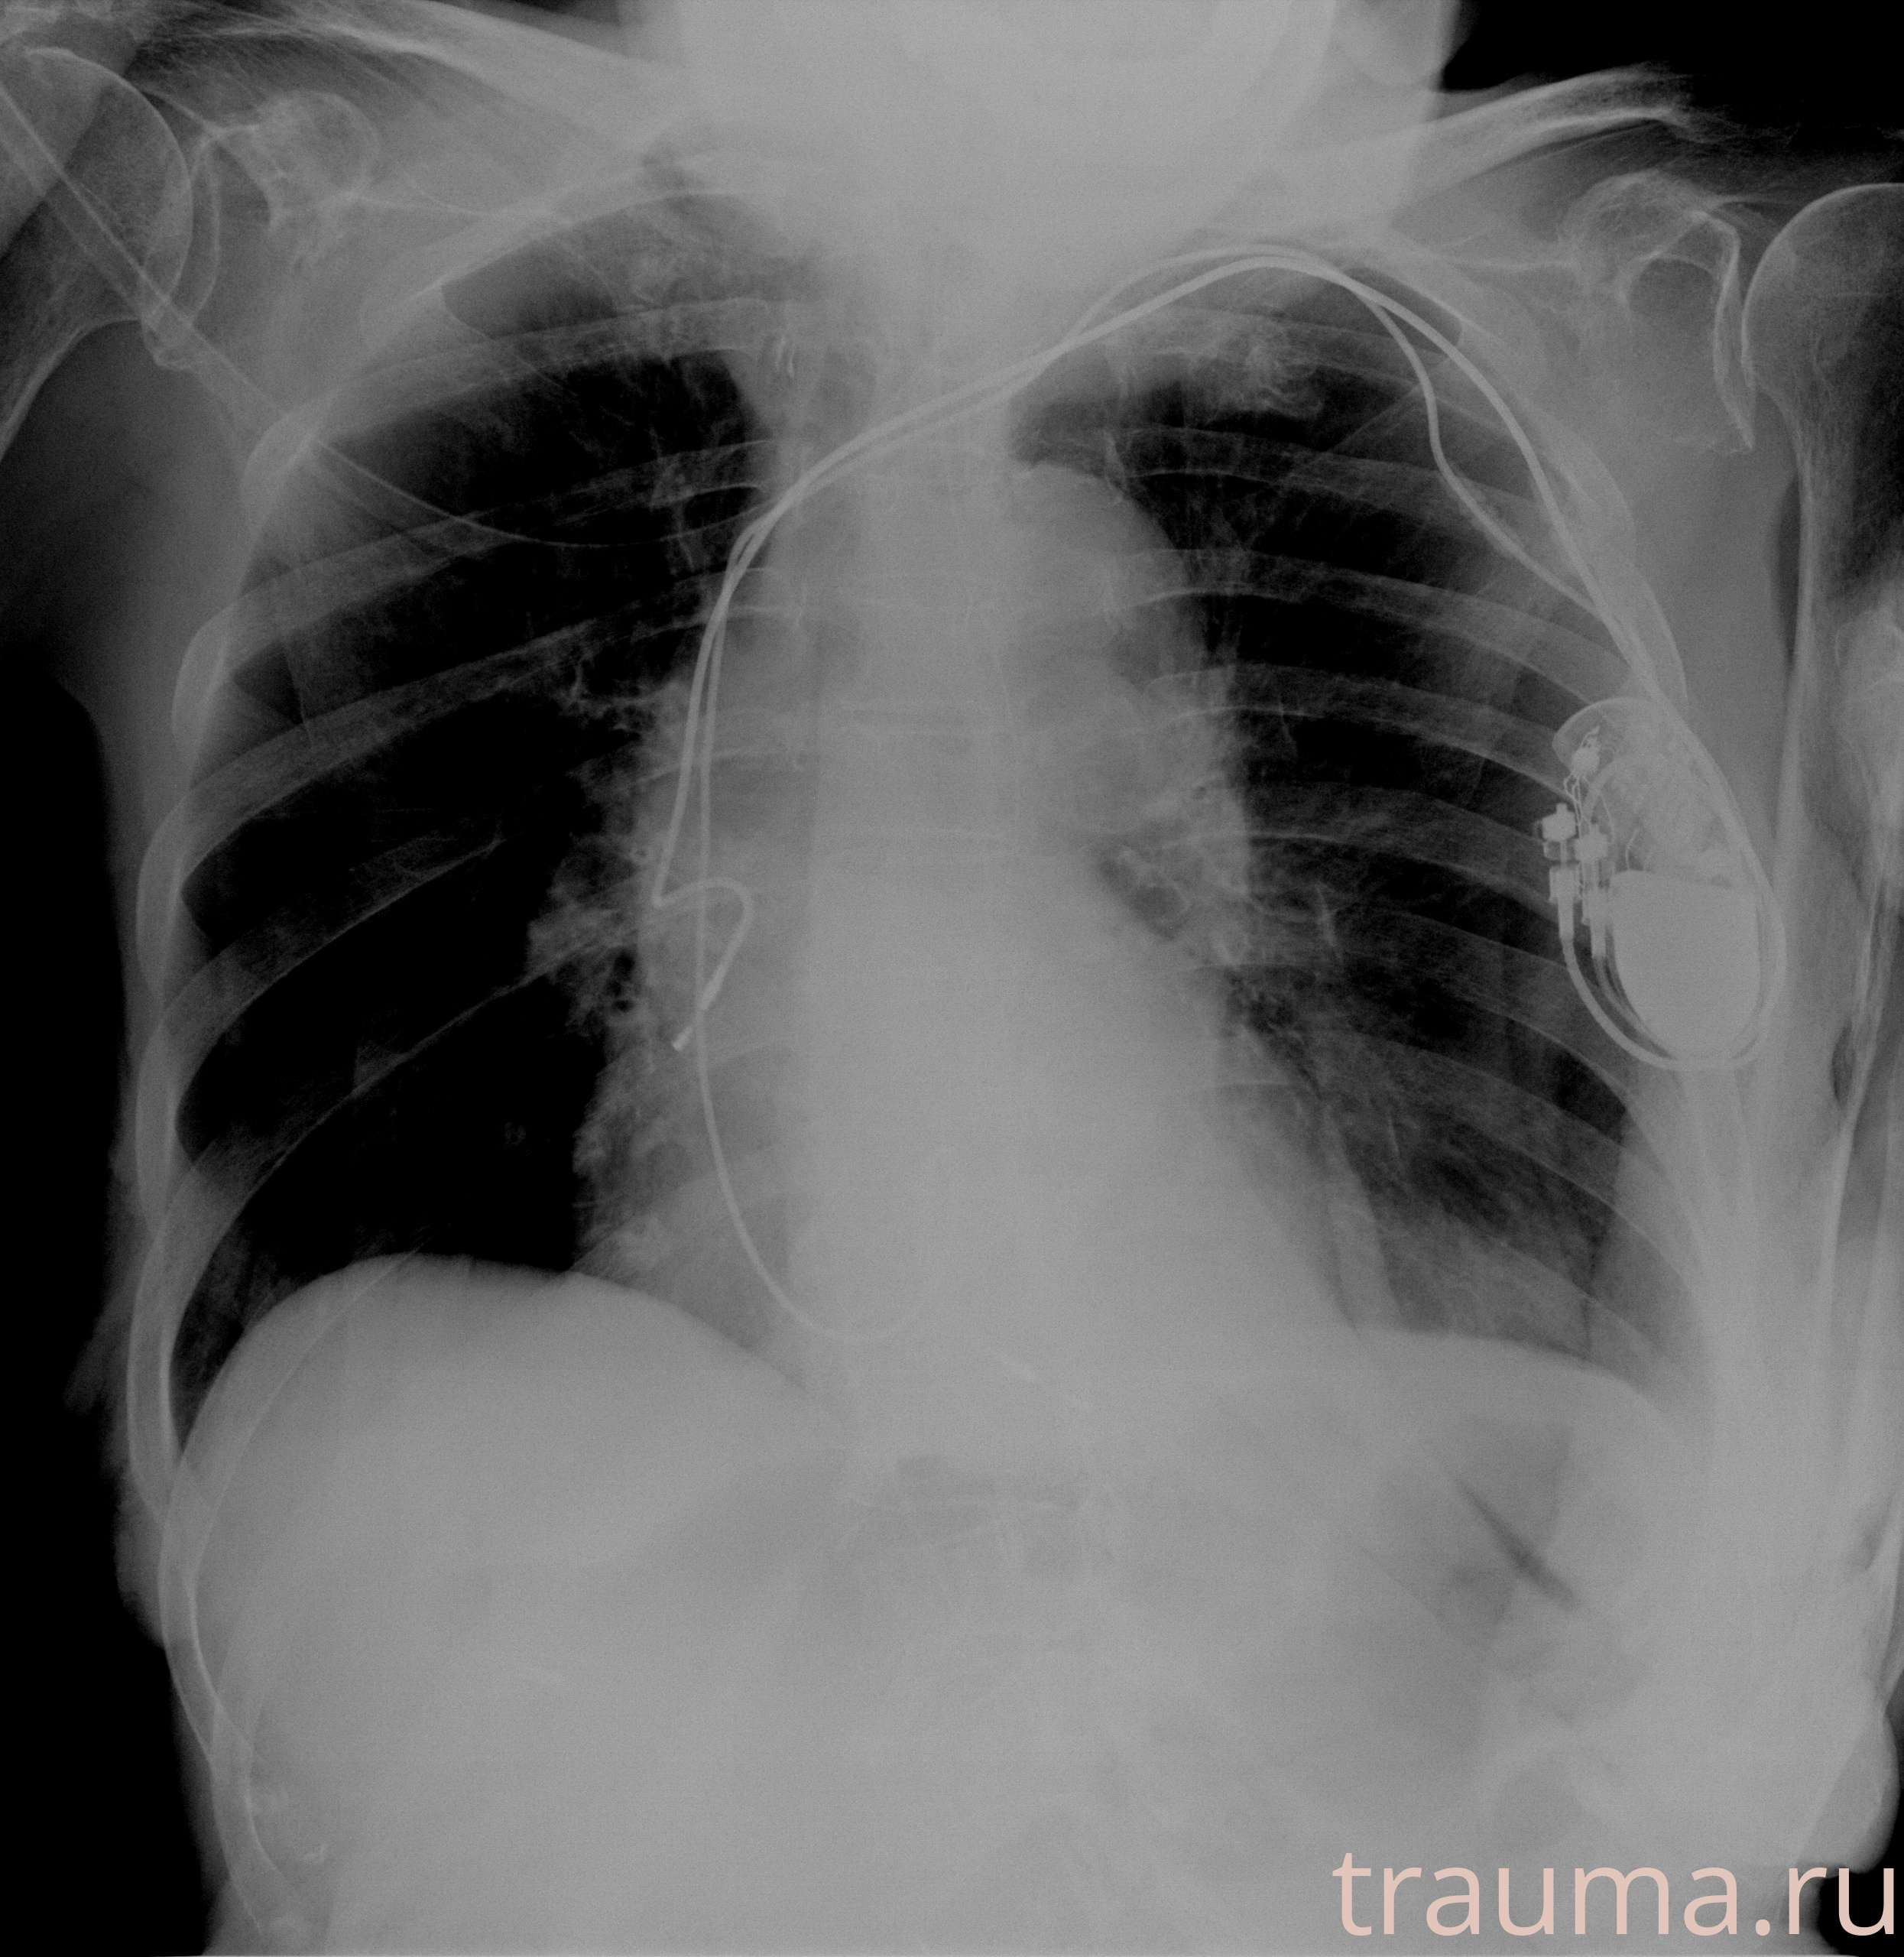

Рентгенограммы

Рентген на дому: по вашему адресу приезжает врач-рентгенолог, травматолог-ортопед с мобильным рентгеновским аппаратом, проводит диагностику травмы или заболевания, делает необходимые рентгенограммы, дает рекомендации по дальнейшему лечению. Получить качественные снимки в домашних условиях возможно благодаря уникальной методике, разработанной МосРентген Центром для института  Склифосовского

при переломе шейки бедра и пневмонии от компании МосРентген Центр - партнера Института имени Склифосовского